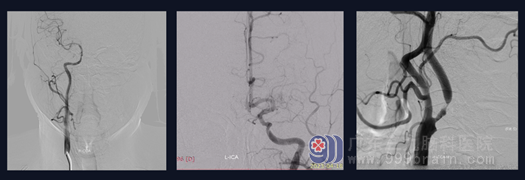

1.1 患者,男,65岁,因“反复头晕3年余”于2023年4月10日入院。患者3年前无明显诱因出现头晕,呈阵发性眩晕,无明显恶心呕吐、天旋地转、四肢乏力等不适,曾到当地医院就诊,予口服药物治疗后出院,出院后患者一般情况可,仍有头晕反复发作,后行头颅CT提示颅内多发脑血管狭窄,现患者及其家属为进一步检查及治疗来我院就诊,门诊拟“颅内多发脑血管狭窄”收住我科。查体:神志清醒,生命体征平稳,言语对答切题,双侧瞳孔等圆等大,直径约2.5mm,对光反射灵敏,视力、视野基本正常,双侧鼻唇沟对称,伸舌居中,颈软,四肢肌力Ⅴ级,感觉、肌张力基本正常,生理反射存在,病理反射未引出。头颅CTA示:左侧颈内动脉起始部管腔局限性狭窄(狭窄度约为82.1%);CTP检查:左侧额顶岛叶、基底节区异常灌注区,考虑为脑梗死前期Ⅰ1期可能,血流灌注较对侧增多;DSA示:1.左侧颈内动脉起始部重度狭窄,长约10mm,程度约70%;2.左侧大脑中动脉M1段闭塞,同侧大脑前动脉开放代偿供血。

图 1 头颅CTA示:左侧颈内动脉起始部管腔局限性狭窄(狭窄度约为82.1%);CTP检查:左侧额顶岛叶、基底节区异常灌注区,考虑为脑梗死前期Ⅰ1期可能,血流灌注较对侧增多。